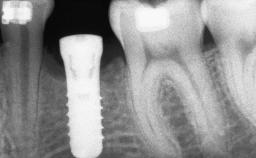

Shell Technique for Horizontal and Vertical Maxillary Bone Augmentation in a Partially Edentulous Patient with Aggressive Periodontal Disease

A 46-year-old woman was referred for treatment whose main complaints were mobility of her fixed partial dentures (right maxilla and left mandible) and periodontal bleeding during function. She also reported having taken systemic antibiotics to treat recurrent swelling in the area of the upper left molars. The patient had not seen a dentist for at least 2 years. She did not smoke and had no history of major systemic disease other than two minor orthopedic procedures some years back. The first-visit examination revealed poor plaque control, tooth mobility, periodontal disease, and a residual dentition widely associated with deep periodontal pockets.

# of Implants 3

Type of Implants One-Piece

Bone Augmentation Horizontal|Staged|Vertical

Bone Volume Deficient vertically or deficient vertically AND horizontally